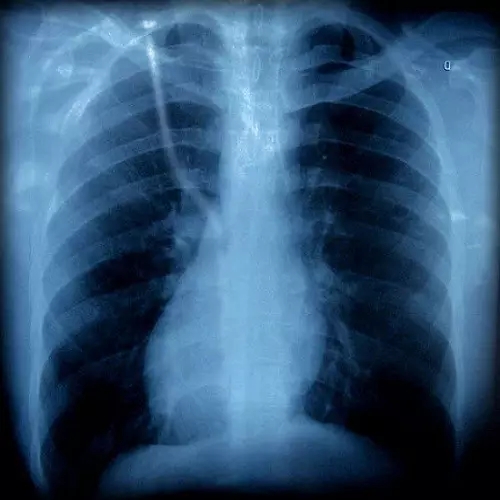

胸片有異

胸外科

咳嗽可以是由肺部腫瘤等疾病引起的,如果胸片或胸部CT上發(fā)現(xiàn)有可疑病變時(shí),應(yīng)該看看胸外科。一般,呼吸內(nèi)科大夫也會(huì)幫忙轉(zhuǎn)診的。